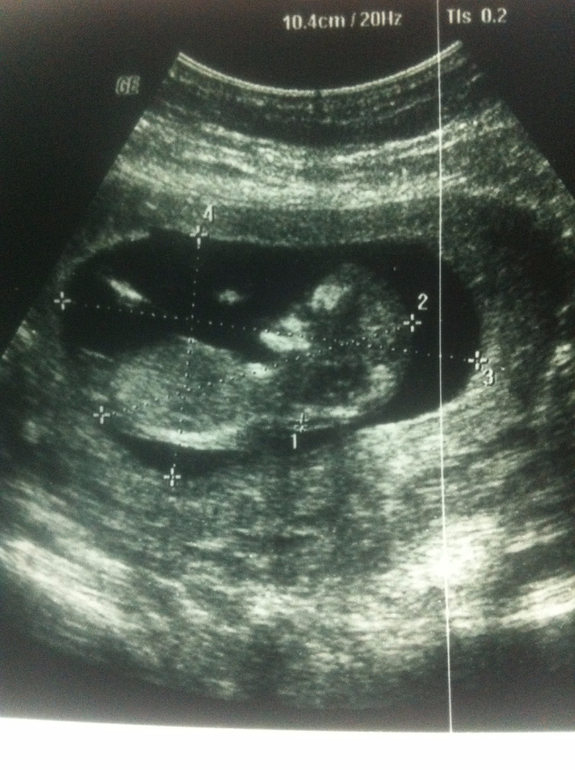

По УЗИ-скринингу всё у нас хорошо. Лапуля наша активно двигается, машет ручкой, зевает))) КТР - 5,8 см, а полная длина плода приблизительно 9 см.

Средний диаметр плодного яйца 5,4 см

КТР 5,8 см

Толщина воротниковой зоны 1,2 мм

Аномалии плода не выявлены

Хорион по задней стенке матки. Толщина 1,7 см

Пуповина визуализируется

Желточный мешок без видимой патологии д=0,5 см

Длина шейки матки 4,2 см внутренний зев сомкнут

БПР= 18,4

ЛЗР= 25,2

ОГ= 69,6 мм

Патологий со стороны плода не выявлено